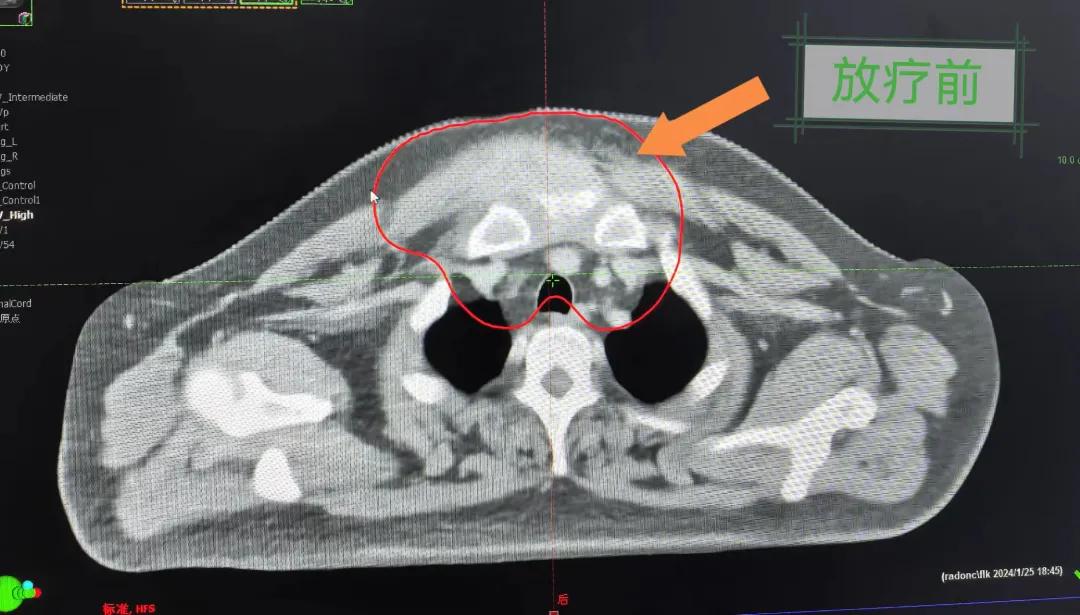

隨后,趙亮主任帶領(lǐng)放療團(tuán)隊(duì)以最快的速度完成了患者的放射治療計(jì)劃,在保證放療精準(zhǔn)打擊腫瘤的同時(shí),利用先進(jìn)的三維立體精確放療技術(shù),最大限度的避免心臟、肺部的損傷發(fā)生,整體治療精準(zhǔn)度達(dá)到1mm以內(nèi)。經(jīng)過(guò)10次的放射治療后,患者疼痛已明顯減輕,胸部腫物肉眼可見的縮小,患者及家屬臉上終于露出久違的笑臉。

治療期間,患者沒有出現(xiàn)明顯不適,治療結(jié)束后,患者胸壁腫物由最初8cm縮小至約1cm,后患者至外科行手術(shù)治療。